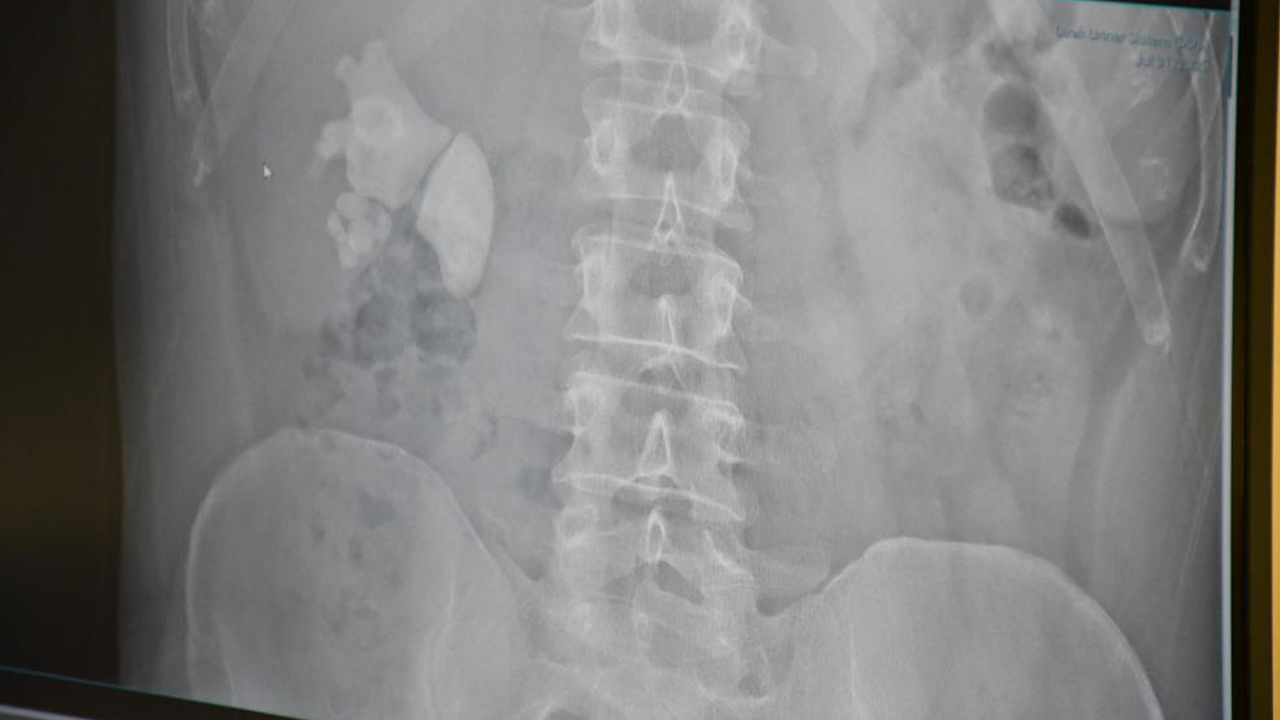

Yapılan detaylı tetkikler sonucunda, Evran’ın böbreğinde 100’e yakın taş tespit edildi.

Kocamanoğlu, “Yaptığımız incelemede sağ böbreğin tamamını dolduran taşlar mevcuttu. Bu tür büyük taşlarda genellikle açık cerrahi düşünülebilir ancak biz hastamıza sırttan tek delikten girerek taşları temizleyebileceğimizi ilettik. Hasta bu yöntemi kabul etti ve başarılı bir operasyon gerçekleştirdik. Neredeyse tüm taşları tek delikten alarak temizledik. Bugün de hastamızı sağlıklı şekilde taburcu edeceğiz” dedi.